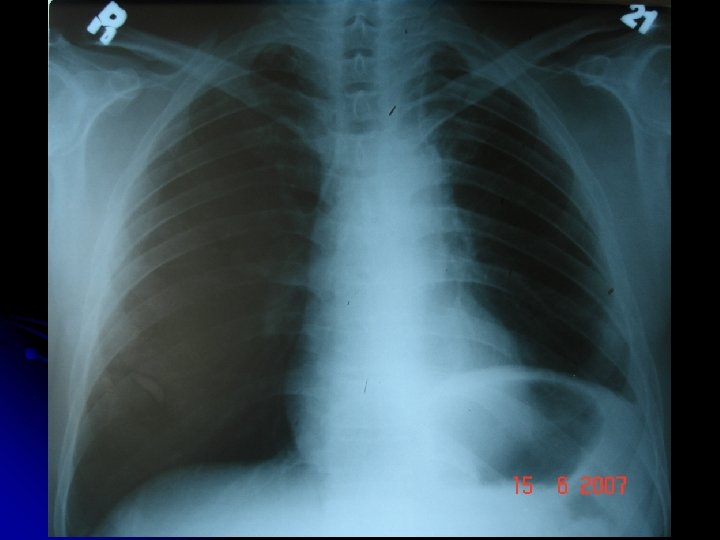

AÇ l 47 yaşında, işçi l Erkek l Doğum yeri: İstanbul l

l ŞİKAYETİ Kuru öksürük Şiddetli sağ yan ağrısı Dispne Aniden şikayetleri başlamış.

l Olası Tanılar? l Plöretik ağrı; Plörezi, l AC infarktı/ AC CA l Pulmoner Emboli l İnf. l Pnömotoraks

FİZİK MUAYENE Siyanoze Dispneik DSS: 32 Sağda hipersonorite OSKÜLTASYONDA Sağda solunum sesi alınmıyor.

l Olası Tanılar? l Pnömotoraks? ? ? l Kitle? ? ?

l Tanı Tedavi